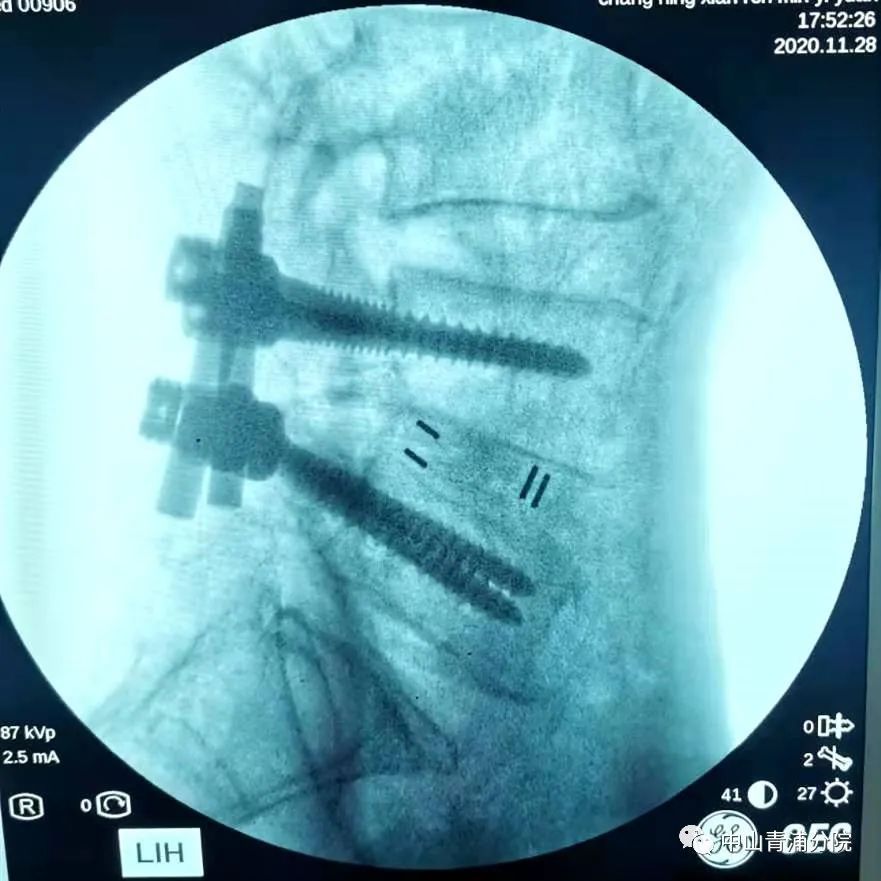

腰椎滑脱减压复位融合内固定手术目前在昌宁县人民医院尚未独立开展,此次骨科的高如锋副主任应邀来到昌宁为两位腰椎管狭窄和滑脱患者手术,同时也是手术示教,希望能将这种技术留在昌宁。